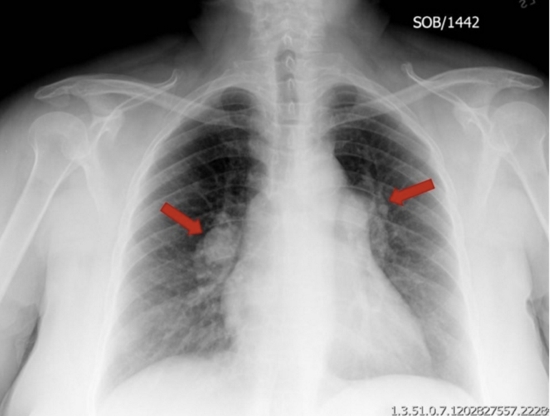

The MRI image above shows bilateral tumors at the cerebellopontine angle (arrows). Most intracranial schwannomas are found at the cerebellopontine angle and are attached to CN VIII. Schwannomas at this location are called acoustic neuromas. Tinnitus, vertigo, and hearing loss are the typical symptoms of an acoustic neuroma. Bilateral acoustic neuromas occur in neurofibromatosis (NF) type 2. NF-2 differs from NF-1 in that it causes fewer cutaneous manifestations and presents with central nervous system involvement.